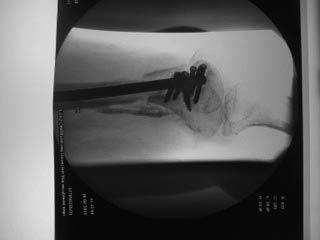

Уважаемые коллеги!Пациентка 72 лет, сочетанная травма в июле 2011. Одно из повреждений (кроме ЧМТ, грудной клетки, длительной реанимации) перелом дистального бедра. После временной фиксации в аппарате через 3 недели накостный остеосинтез. Раннее нагноение, попытки консеравативного лечения. Под наше наблюдение попала через 6 месяцев, гнойный свищ по наружной поверхности бедра, до пластины, нестабильная фиксация,миграция винтов, боли, постельный режим. Первым этапом удалена пластина, некрэктомия, бусы из цемента с а\б, апааратная фиксация. Заживление первичное. Вторым этапом снятие аппарта через месяц, замена бус, интрамедуллярный остосинтез, в последующем (через 1,5 месяца) бусы удалены, введены дополнительные винты из-за начинающейся миграции. Заживление первичное. В настоящее время 7 месяцев после последнего вмешательства, гвоздь динамизирован. На фоне улучшения общего состояния (пациенка активизирована, ходи с доп.опорой, болевой синдром незначительный) сохраняются эпизоды гипертермии проходящие на фоне а\б широкого спектра (авелокс). Р-граммы в динамике - отсутствие признаков нестабильности, резорбции, динамизация не исчерпана.Основная проблема - гипертермия, возобновляющаяся через 2-3 недели после прекращения а\б. Варианты:1) Наблюдать до 12-18 месяцев надесясь на консолидацию с последующим удалением 2) некрэктомия? 3) Резекция в пределах здоровых тканей с онкологическим протезом? Другие варианты

У меня пока складывается впечатление, что надо бы удалить гвоздь, поправить ось и пересинтезировать гвоздем с покрытием. Сейчас есть вальгус, гвоздь очень спереди, в дистальном отломке держится плоховато. То есть улучшить соотношение отломков и увеличить стабильность. Плюс рассверлить.

Про переднее положение гвоздя- это есть, но он точно в дистальном отломке, Сместить кзади не получилось из-за множественных дефектов от пластины, пороза, отклоняющие спицы просто режутся

Действительно, смущает близкое расположение гвоздя к переднему кортикалу в дистальном отломке - это явно не добавляет стабильности. И если есть возможность увеличить стабильность - надо ее использовать. Да местное депо антибиотиков будет не лишним.